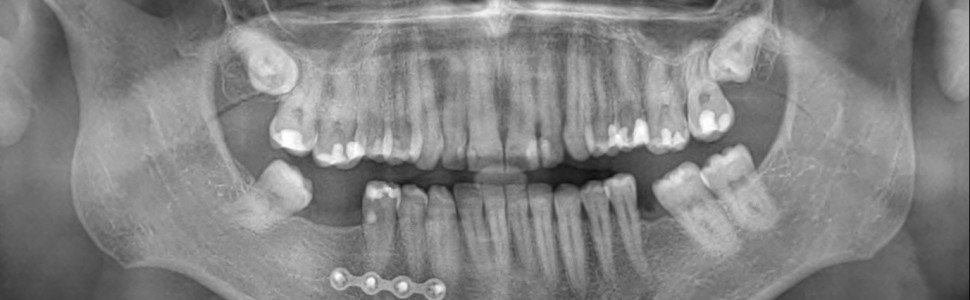

Opis przypadku przedstawia leczenie endodontyczne drugiego zęba przedtrzonowego żuchwy po stronie prawej (ząb 45) z powodu resorpcji wewnętrznej perforującej korzenia zęba. Głównymi dolegliwościami, z którymi pacjent zgłosił się do gabinetu były ból przy nagryzaniu i krwawienie z brodawki dziąsłowej pomiędzy zębami 44-45. W badaniu przedmiotowym stwierdzono dodatnią reakcję na perkusję pionową i poziomą, brak reakcji zęba 45 w teście żywotności z użyciem chlorku etylu oraz kieszonkę przyzębną od strony mezjalno-policzkowej o głębokości 7 mm. Badanie tomografii stożkowej CBCT wykazało resorpcję wewnętrzną korzenia zęba perforującą w stronę mezjalno-policzkową. Plan leczenia zakładał jednowizytowe leczenie endodontyczne mające na celu usunięcie ziarniny resorpcyjnej, histologicznie zmienionej miazgi zęba, szczelne wypełnienie systemu endodontycznego, jamy resorpcyjnej i perforacji termoplastyczną gutaperką oraz materiałem BIO MTA+. Efekty leczenia oceniono w badaniu klinicznym i radiologicznym po 6 miesiącach od zakończenia terapii. Pacjent zgłaszał ustąpienie dolegliwości, a badanie CBCT ukazało prawidłowy obraz radiologiczny. Autorzy wskazują na zasadność podjęcia terapii endodontycznej w przypadku resorpcji perforującej korzenia zęba z wykorzystaniem materiałów bioaktywnych, mającej na celu zachowanie własnego zęba.

The case report shows root canal treatment of the mandibular second premolar on the right side (tooth no. 45) due to perforating internal root resorption. The main complaints with which the patient came to the office were pain on biting and bleeding from the gingival papilla between tooth 44 and 45. The physical examination revealed a positive reaction to vertical and horizontal percussion, no reaction in the viability test using ethyl chloride and a periodontal pocket from mesiobuccal side, 7 mm deep. CBCT examination showed mesiobuccally perforating internal root resorption. The treatment plan assumed a one-visit root canal therapy aimed at removing resorption tissue, histologically changed tooth pulp, hermetic filling of the endodontic space, resorption cavity and perforation with thermoplastic gutta-percha and BIO MTA+ material. After endodontic treatment, they were assessed by clinical and radiological examination 6 months after the end of therapy. The patient's symptoms disappeared and the CBCT examination showed a normal radiological image. The author’s points out the validity of endodontic treatment of internal perforating root resorption using bioactive materials aimed at preserving one's own teeth.